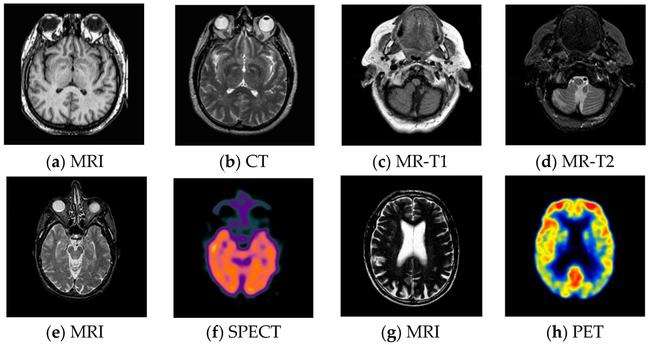

我们来看,就是当一个人的记忆力开始明显减退,那么他在大脑里发生了什么?首先,研究人员利用MRI(MRI就是我们平时说的核磁共振),对记忆力明显衰退的老年失智症的患者的大脑的形态学进行了显像,结果发现,绝大多数老年性失智症患者或者正在进行中的老年性失智症患者的大脑,都发生了不同程度的形态学的改变,最常见的就是脑萎缩。

那么MRI发现,大多数老年失智症患者,他的脑沟是变浅了,脑沟变宽了,或者是相反,脑回变宽了,但是脑沟变深了,就像人的脸,老了以后褶皱特别多就变得不那么平滑,不那么规则了。这是就是MRI所观察到的情景。

那么,对老年失智症的更细的研究,还依赖于功能性的显像,功能性的脑显像,主要是PETPET/CT,PET/MRI还有SPECT这些功能性的,可以在活体状态下动态地观察人脑的运作状态。

结果通过PET 和SPECT研究发现,老年失智症患者或者具有这种倾向的人,包括记忆力减退的人都有不同程度的脑功能的异常改变,主要表现在:颞叶内侧的生理机能水平比正常人降低了部分的患者,是顶叶皮质的葡萄糖摄取降低或者是血流灌注降低。

如果真的发展成老年痴呆症,那最典型的脑影像就是整个脑皮质变薄了,大脑的生理机能水平整体性地降低了,尤其以颞叶和顶叶的生理机能减退更为明显。关于这一点,大家可以看这方面的科普材料。